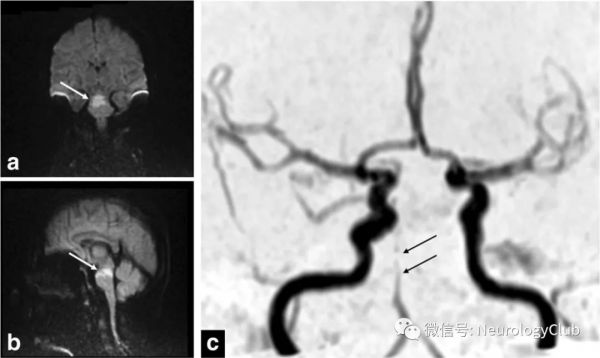

MRI-DWI序列被认为是诊断后循环卒中的金标准,头颅MRI检查诊断眩晕/头晕患者缺血性卒中的灵敏度为83%,特异度为96%。研究认为,当怀疑为PCI导致的AVS患者在以下情况时建议完善头颅MRI检查:1)伴有局灶神经功能缺损的症状或体征;2)表现为孤立性AVS的老年患者,合并多重血管病危险因素;3)孤立性AVS合并新近出现的头痛,尤其是枕部头痛;4)既往无梅尼埃病病史,有血管病危险因素的患者出现眩晕和耳聋急性发作;5)患者HIT阴性、有凝视性方向变化的眼震或严重步态不稳,甚至行走时会倾倒,合并血管病危险因素。尽管如此,MRI对后颅窝病变的检出率可能不如前循环病变,在发病24h内,后循环卒中的DWI存在20%的假阴性。常规MRI很少能够发现位于后颅窝的部分孤立性小梗死灶,因此,在早期MRI阴性的情况下,不应排除PCI,需结合患者的临床表现、眼动检查及动态MRI检查结果进行综合判断。

(插图3:MRI显示基底动脉闭塞;a-b:DWI可见脑桥上部的超急性缺血性改变;c:MRA可见中段基底动脉闭塞[箭];引自:Sparaco M, Ciolli L, Zini A. Posterior circulation ischemic stroke-a review part II: imaging and acute treatment. Neurol Sci. 2019 Oct;40(10):2007-2015.)